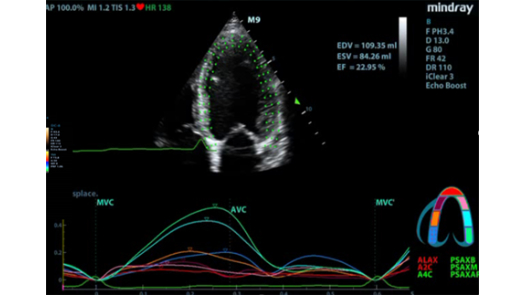

Оценка движения миокарда методом спекл-трекинга и количественный анализ ZST+

- Отличное качество изображения в B-режиме для точного диагноза

- Поддержка анализа в онлайн-режиме и режиме постобработки